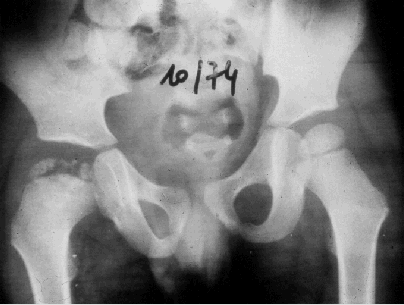

Illustration 6 : Stade très avancée : fragmentation de l'épiphyse droite (d'après [3]).

Illustration 7 : Coxa plana à droite.

Illustration 6 : Stade très avancée : fragmentation de l'épiphyse droite (d'après [3])

Illustration 7 : Coxa plana à droite